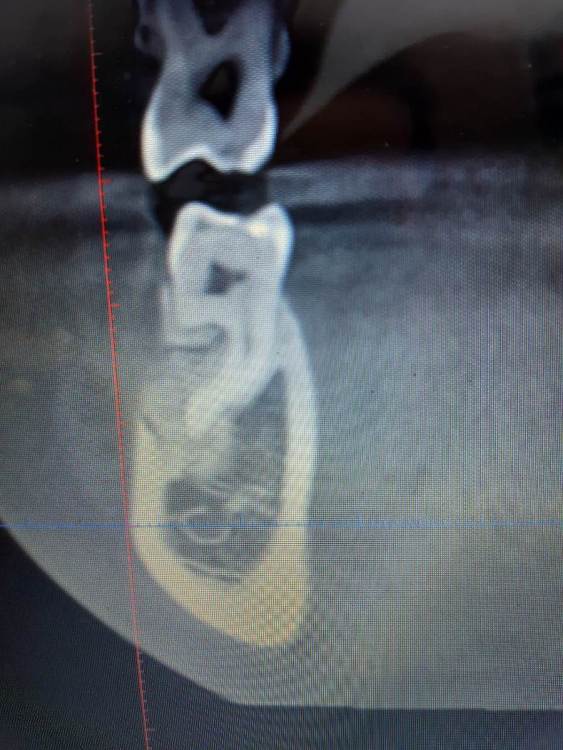

Доброго времени суток, коллеги! Кто может посмотреть КТ, делали по другому поводу, случайно найдено образование. Не беспокоило все это время. На оптг за 2019 год ничего такого не видно. Неужели придется удалять зуб вместе с образованием?

20210511_210029.jpg